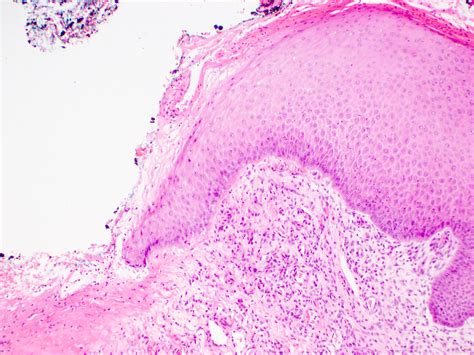

• Biopsy: A small sample of the affected tissue may be taken for further analysis.